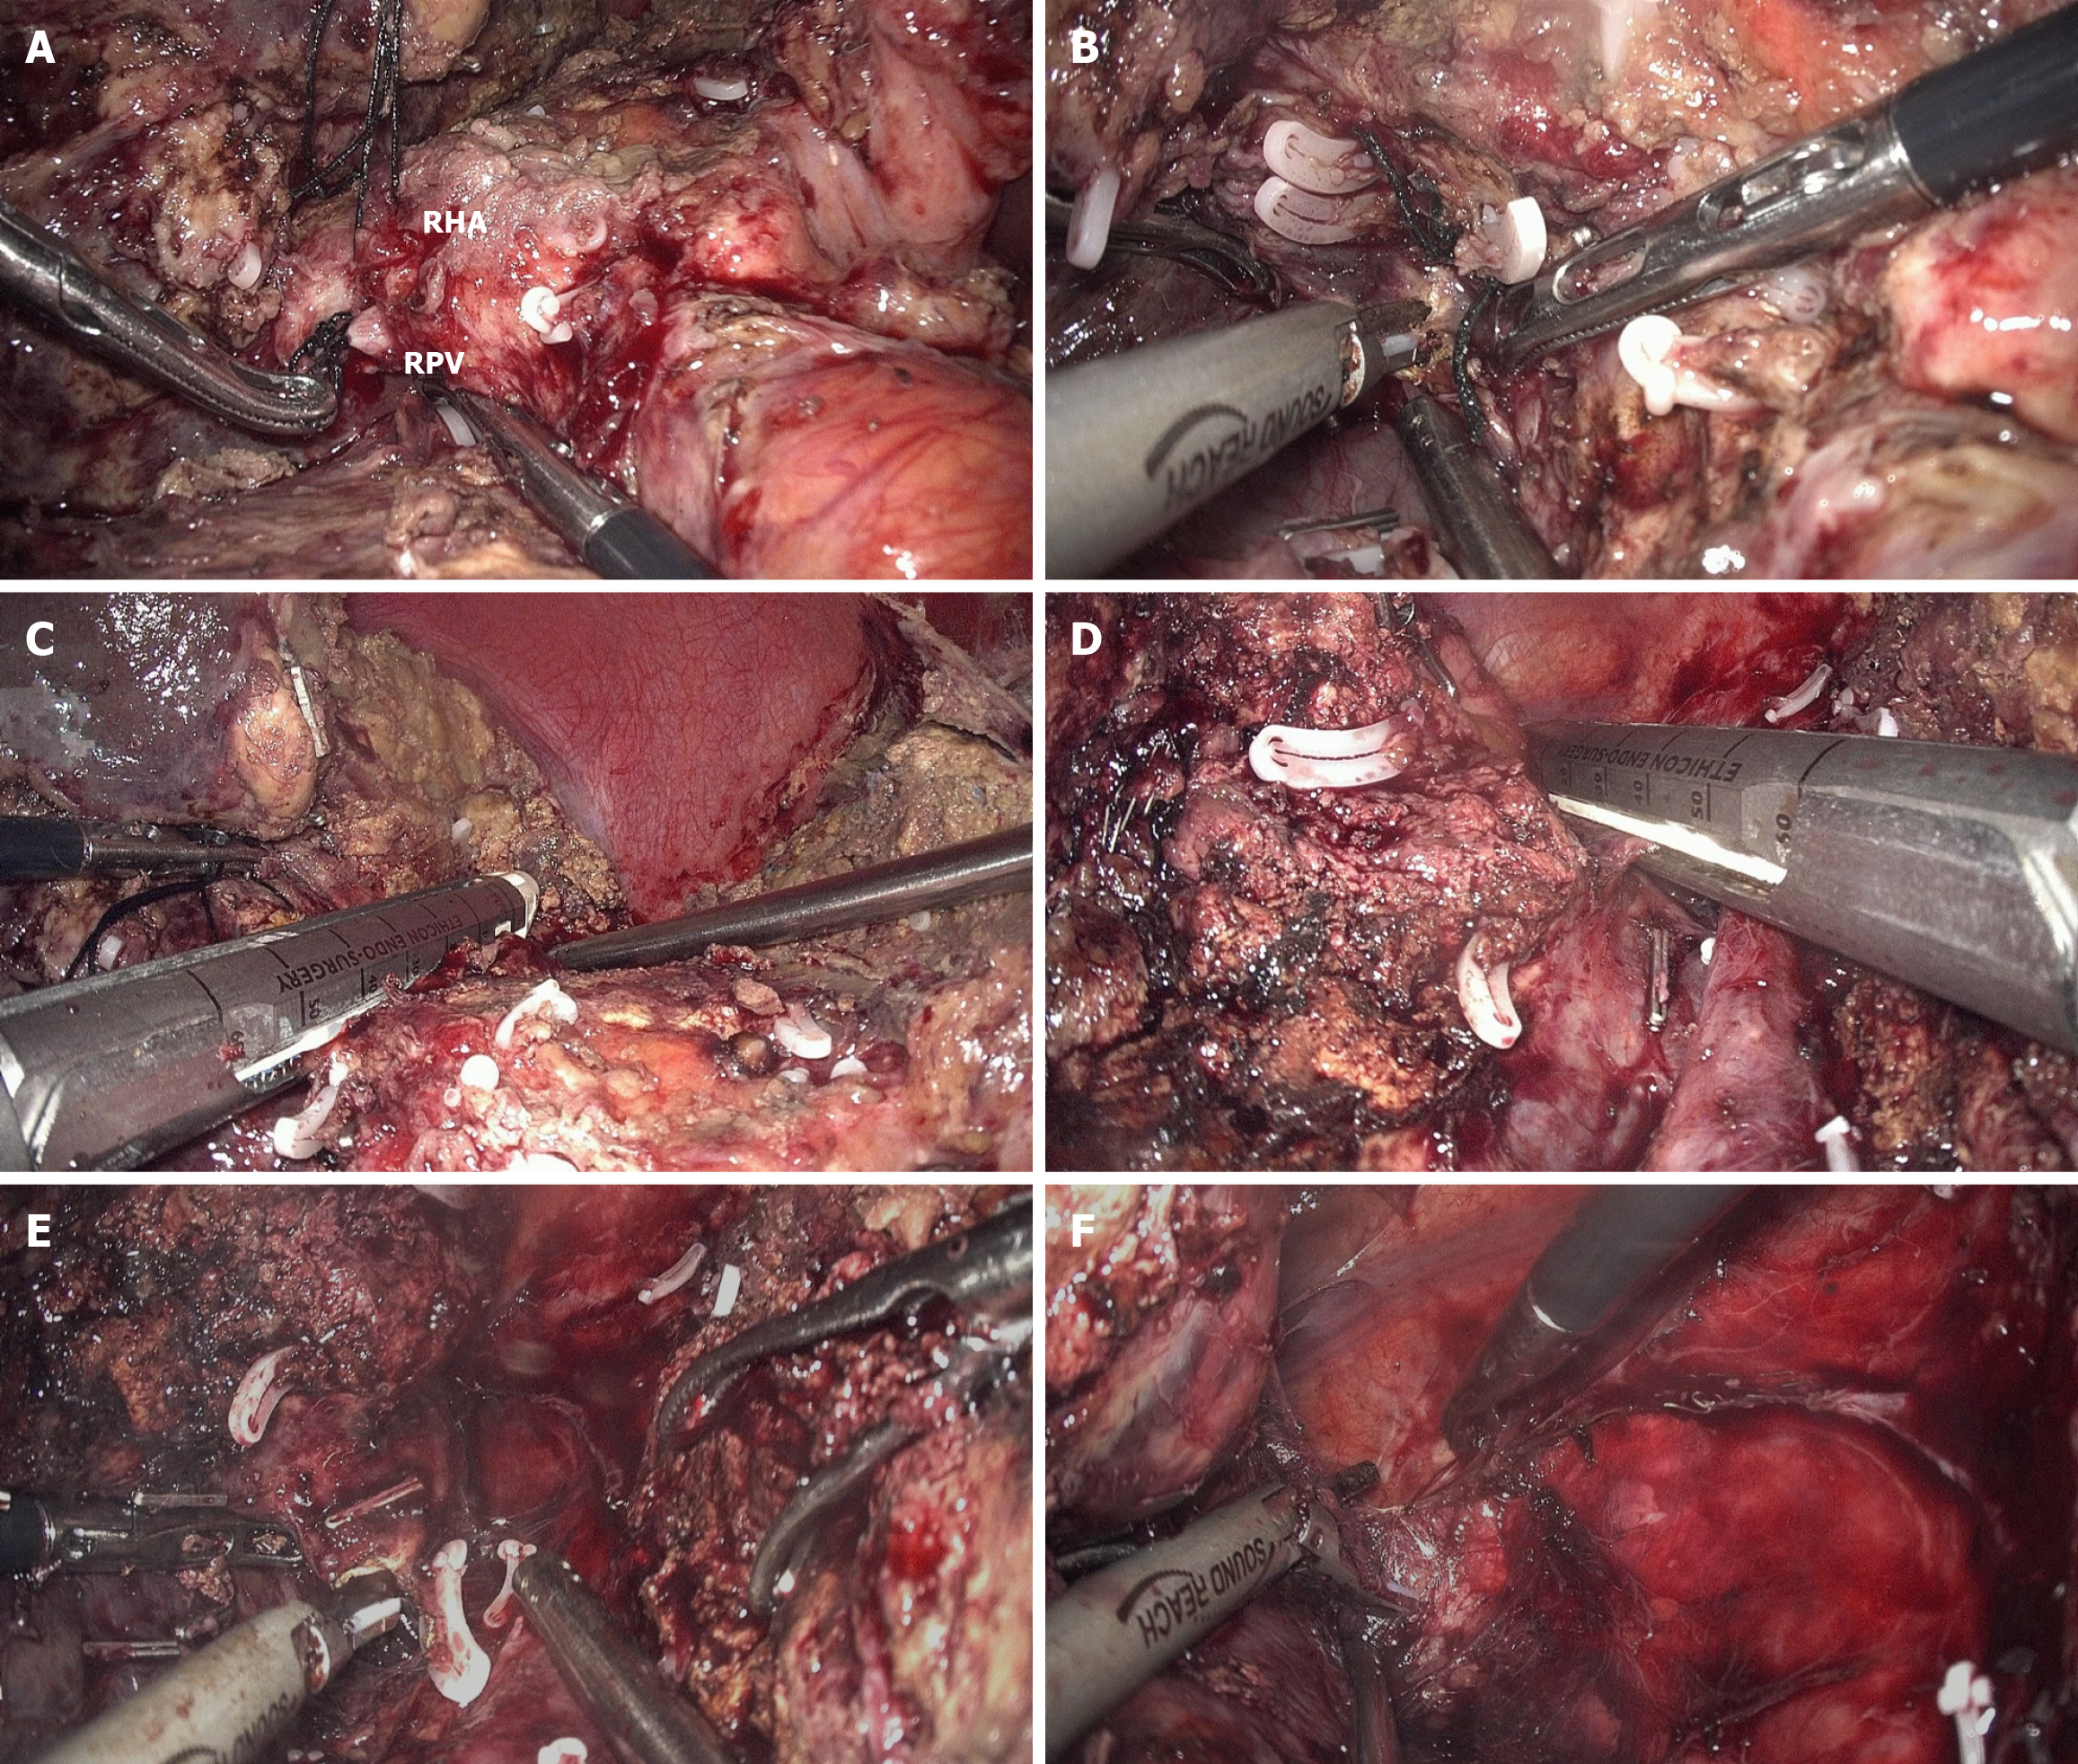

Figure 3 Main procedures in stage 2 of full laparoscopic associating liver partition and portal vein ligation for staged hepatectomy.

A: Identification of the right hepatic artery (the single long loose suture) and right portal vein (the double short tight sutures); B: After transection of the right hepatic artery and right portal vein, dissection of the space posterior to the right Glisson pedicle is taken; C: Division of the right Glisson pedicle by endostapler; D: Transection of the right hepatic vein by endostapler; E and F: Completely mobilization of the right liver as the final step of stage 2. RHA: Right hepatic artery; RPV: Right portal vein.